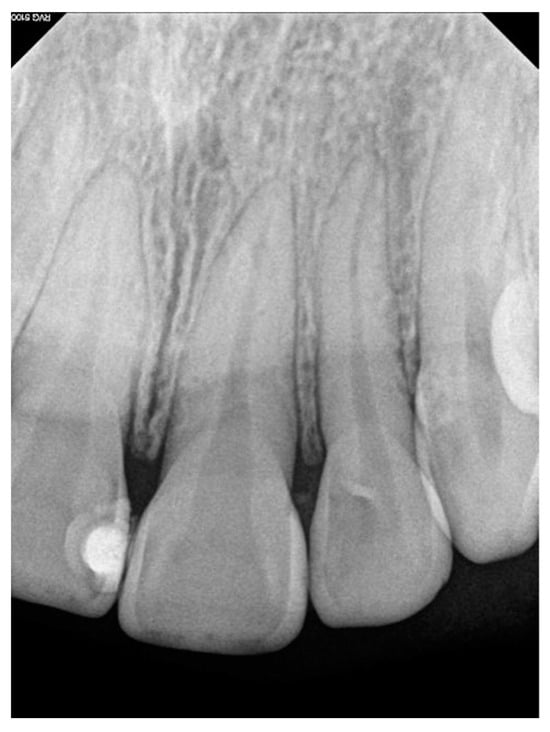

Intraoral clinical examination identified an increase in the volume of the gum (measuring 1.0 cm × 0.7 cm × 0.3 cm) located between the central and upper left lateral incisors, and partially filling the vestibular space. On palpation, the area presented a soft consistency, a rough texture, an oval base with slight mobility, and a pink coloration with irregular margins but without bleeding or pain (Figure 1). Furthermore, a probing depth of 9 mm was recorded vestibularly. Subgingival calculus and plaque were present. Contradictorily, there were no signs of dental mobility and the patient referred no symptomatology. Intra-oral peri-apical radiograph revealed no pathological findings or any signs of bone loss, root resorption, or increased periodontal ligament space (Figure 2). A complete blood count was performed and all blood results were within normal limits. Based on the information obtained from the historical, clinical, and radiographic examinations, a presumptive diagnosis of pyogenic granuloma or PGCG was considered.

Figure 1. Preoperative clinical view of PGCG in the patient, showing an increase in gum volume corresponding to the circumscribed and well delimited lesion between maxillary central and lateral incisors. (A) Frontal view; (B) lateral view.